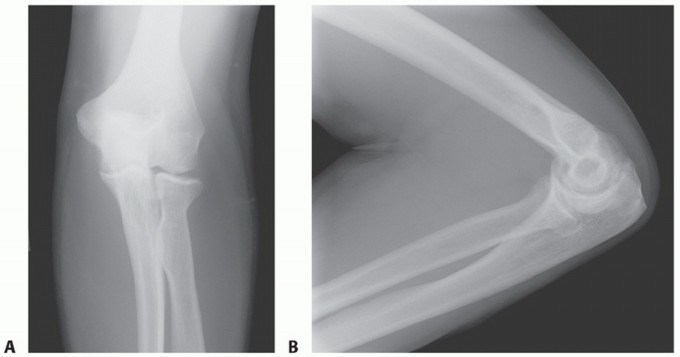

DEFINITION Fracture of the olecranon process is common, usually displaced, and nearly always treated operativ…